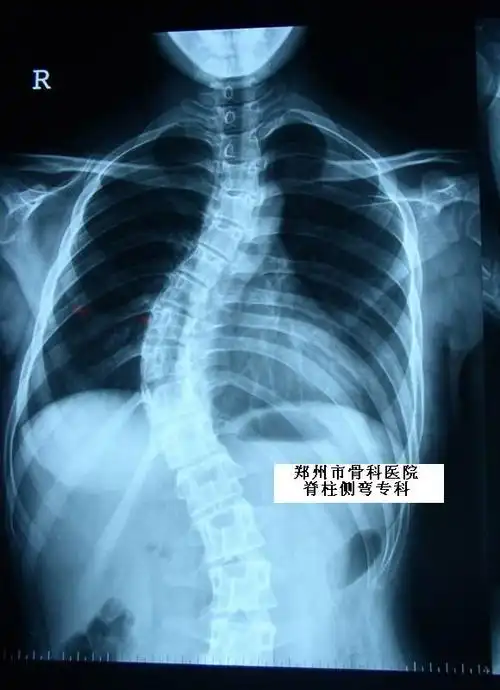

病例:女,14岁,特发性脊柱侧凸,中华长城三维矫正术后.